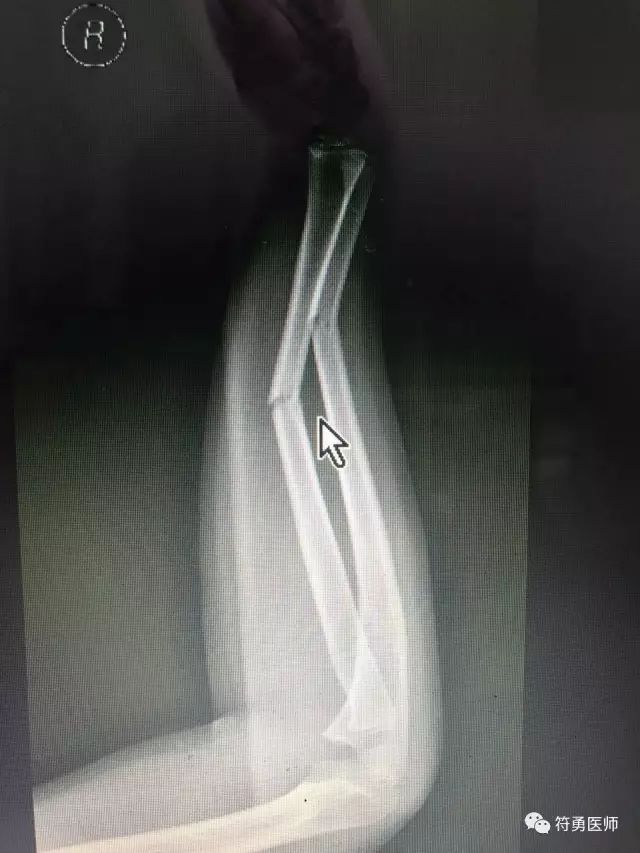

上图:摔伤后前臂骨折错位